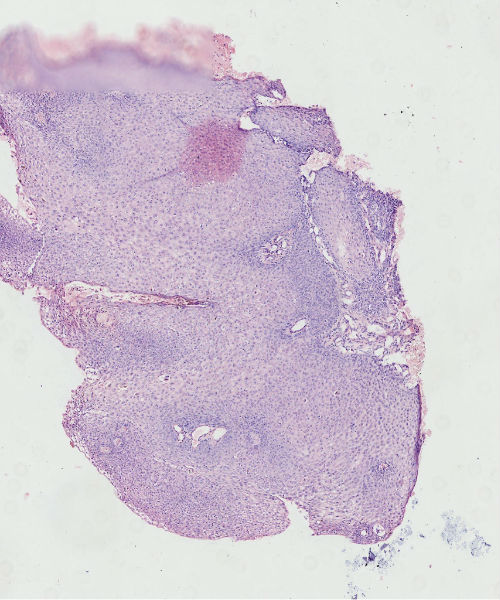

女45岁,宫颈口可见一突出物直径约0.5菜花状质脆

乳头状的CIN,有平切,似乎有高级别的CIN,需除外癌。

CIN3,伴湿疣感染

细胞异型性不太大,考虑湿疣样增生

细胞异型不大,乳头状瘤。